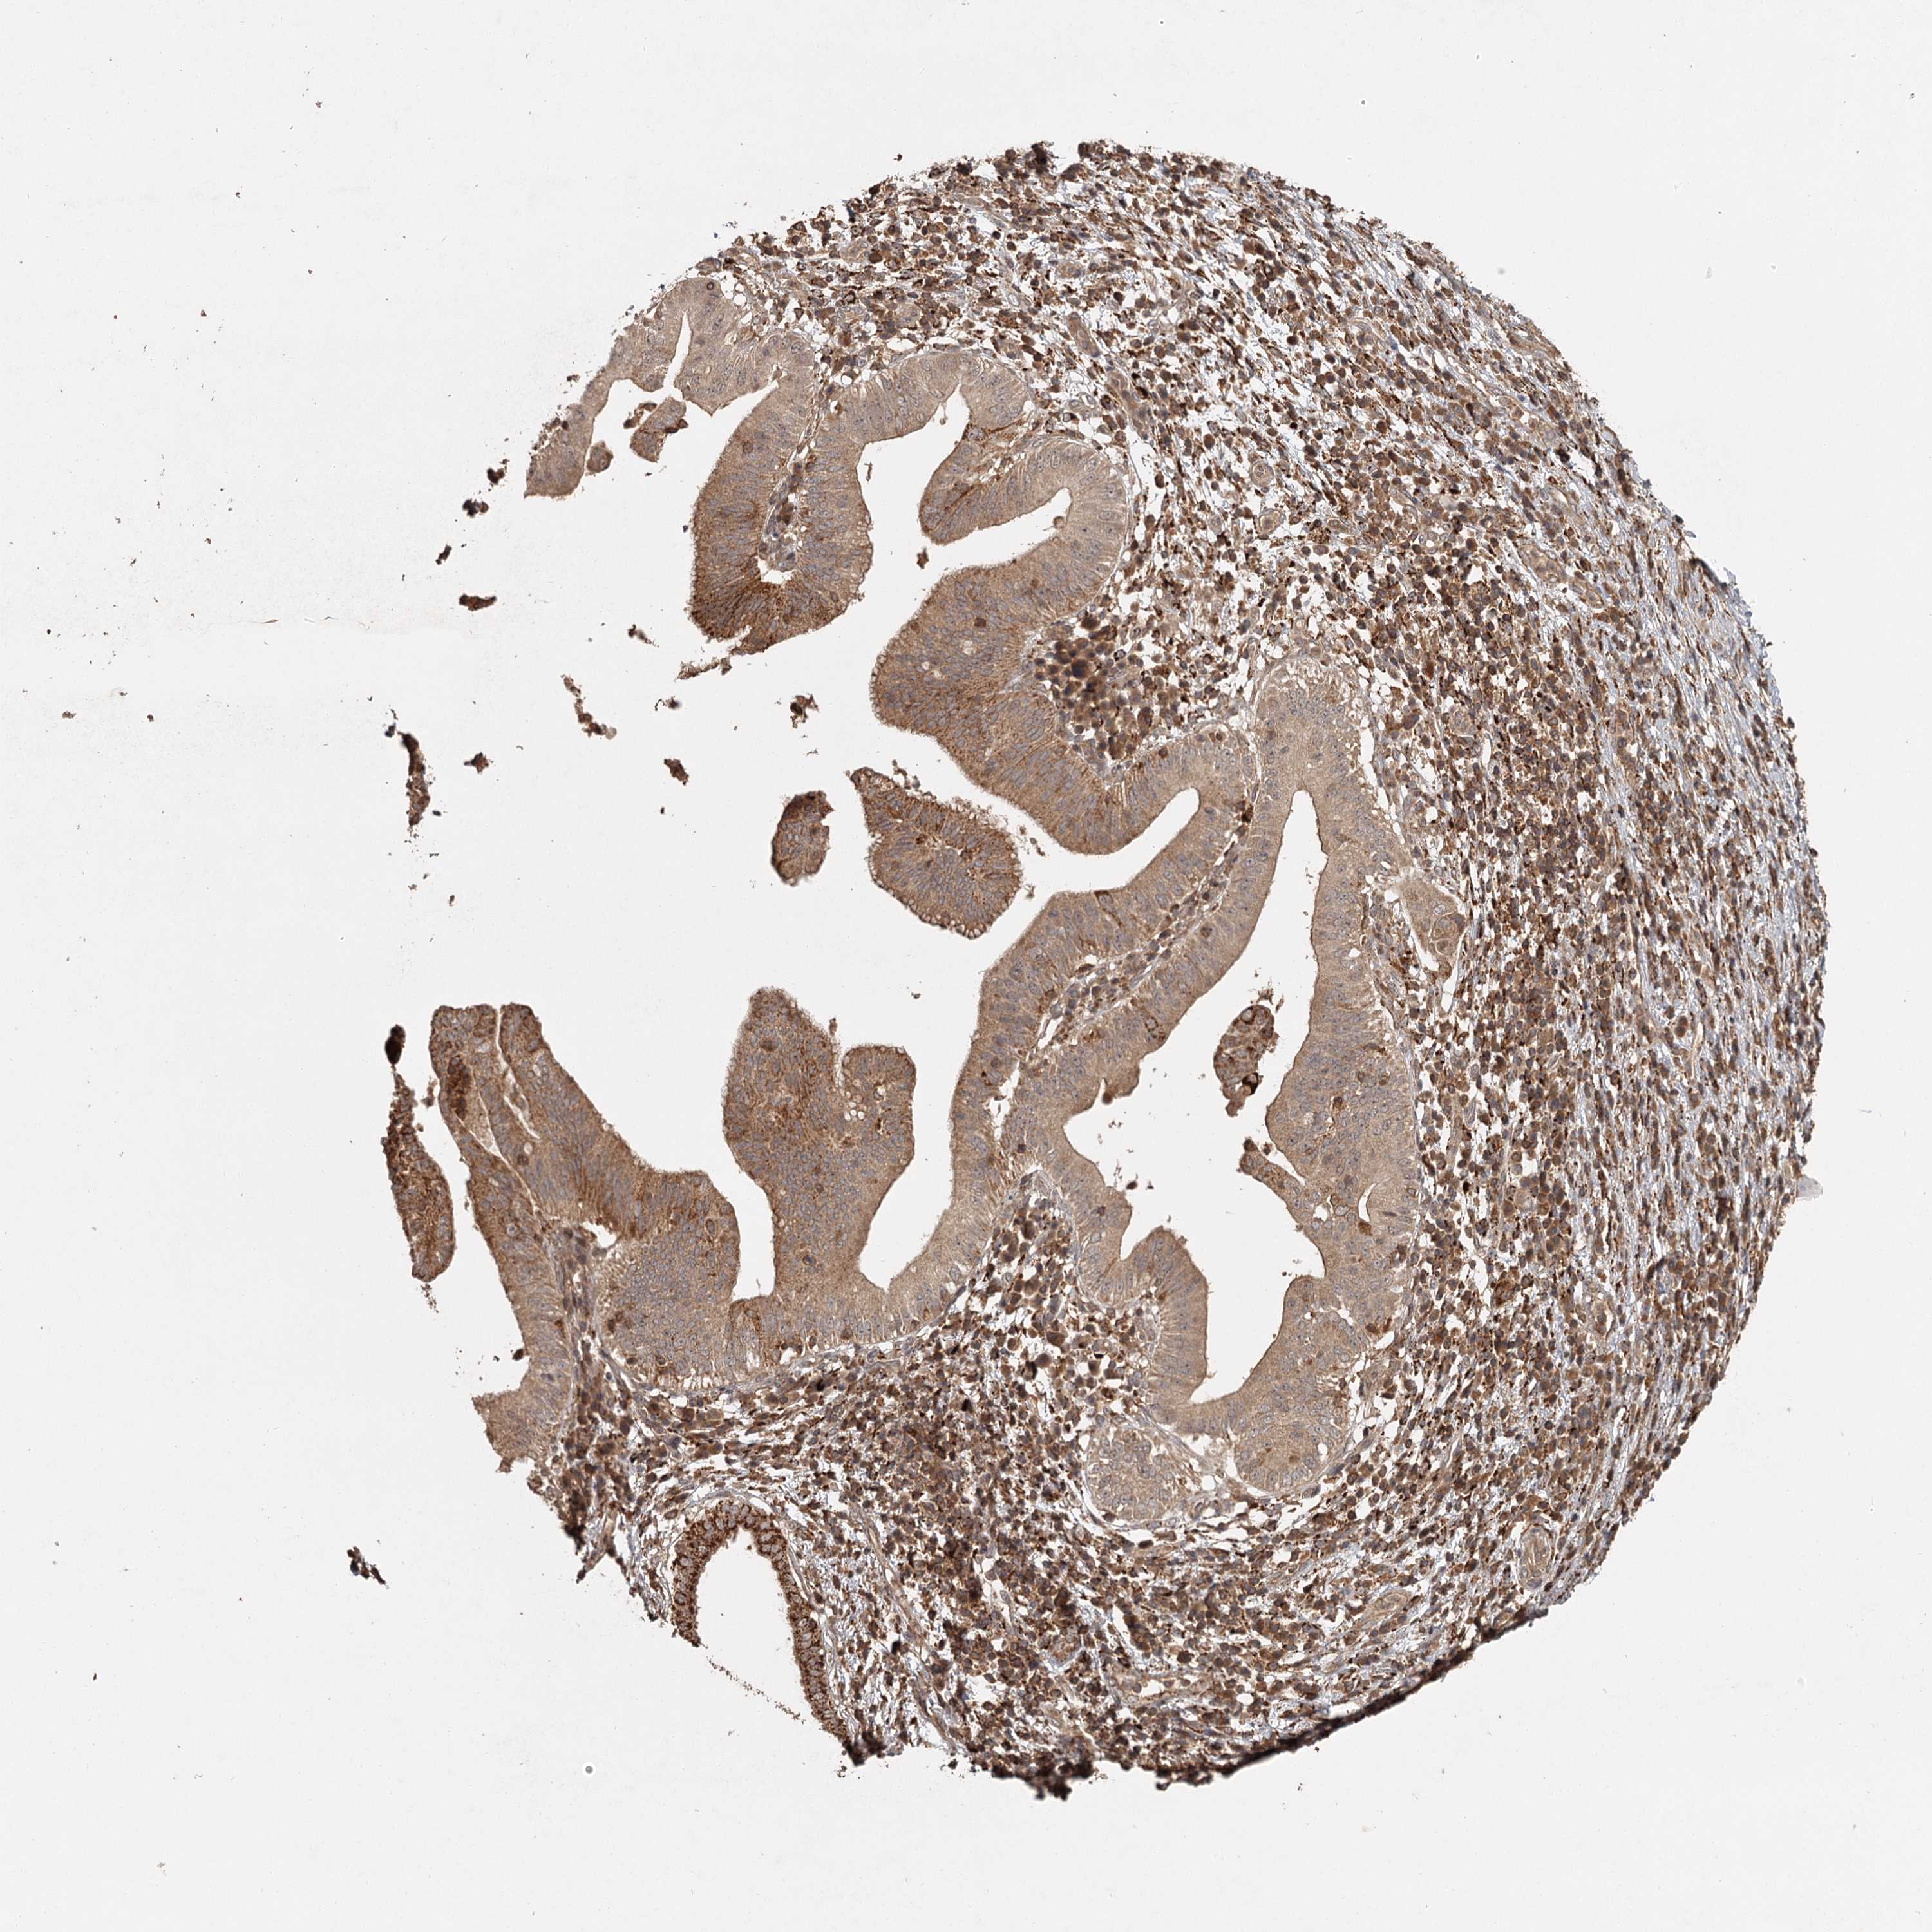

PANCREATIC CANCER - Protein expressioni

A mouse-over function shows sample information and annotation data. Click on an image to view it in a full screen mode. Samples can be filtered based on level of antibody staining by selecting one or several of the following categories: high, medium, low and not detected. The assay and annotation is described here.

Note that samples used for immunohistochemistry by the Human Protein Atlas do not correspond to samples in the TCGA dataset.

Antibody stainingi

Antibody staining in the annotated cell types in the current human tissue is reported as not detected, low, medium, or high, based on conventional immunohistochemistry profiling in selected tissues. This score is based on the combination of the staining intensity and fraction of stained cells.

Each image is clickable and will lead to virtual microscopy that enables deeper exploration of all samples and also displays staining intensity scores, fraction scores and subcellular localization as well as patient and tissue information for each sample.

Antibody HPA039106

Staining

High

Medium

Low

Not detected

Intensity

Strong

Moderate

Weak

Negative

Quantity

>75%

75%-25%

<25%

None

Location

Nuclear

Cytoplasmic/membranous

Cytoplasmic/membranous,nuclear

Adenocarcinoma, NOS